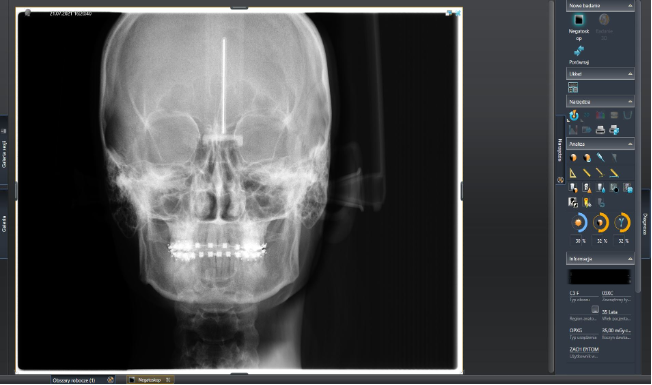

ZDJĘCIA CEFALOMETRYCZNE- integralna część oceny ortodontycznej. Główne wskazania kliniczne pod kątem ortodoncji i chirurgii szczękowo twarzowej. Wskazania ortodontyczne to: wstępna diagnoza-potwierdzenie nieprawidłowości szkieletu kostnego i / lub tkanek miękkich, planowanie i ocena wyników leczenia. Wskazania chirurgiczne: przedoperacyjna ocena kości twarzoczaszki i tkanek miękkich, pooperacyjna ocena rezultatów operacji.